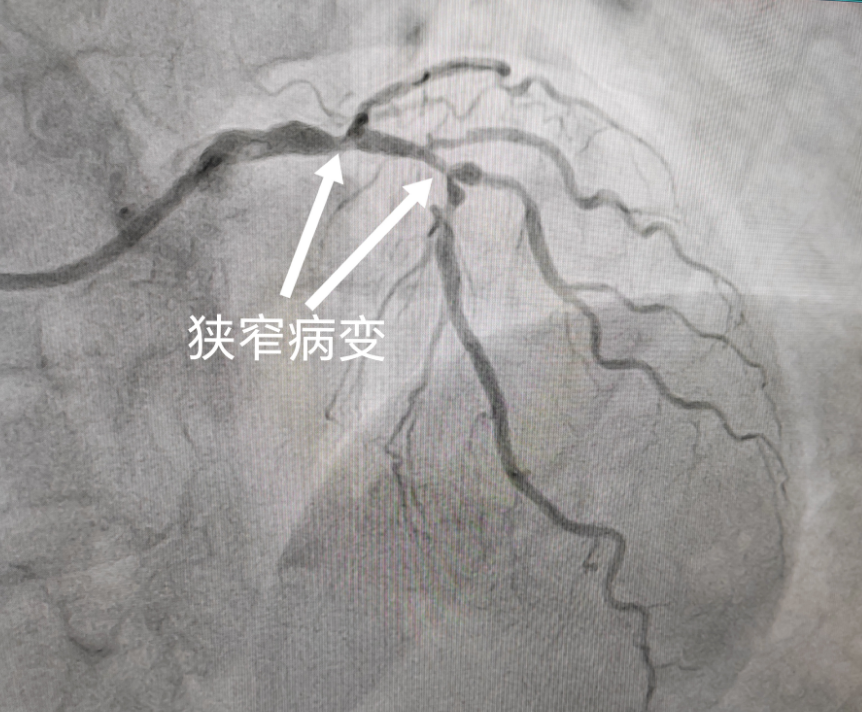

一个月前,77岁的张阿姨来到北京中医医院内蒙古医院心病科主任、北京常驻专家李爱勇门诊就诊,一进门,张阿姨着急的说:“李主任,我最近胸口痛的厉害,但我不想搭桥,您能帮我想想办法吗?”,李爱勇主任详细询问患者现、既往病史,看到张阿姨之前的相关检查资料,饶是经验丰富的李爱勇主任也不由得皱起眉头。原来,张阿姨曾做过冠状动脉造影,右侧冠状动脉植入过一枚支架,但左主干及前降支均存在严重狭窄病变,外院建议行冠状动脉旁路移植术(搭桥),张阿姨听说北京中医医院内蒙古医院来了北京常驻专家坐诊,便来寻求帮助,希望行冠状动脉介入治疗(支架)。

冠状动脉左主干病变是指冠状动脉造影显示左主干直径狭窄程度≥50%的病变,约占总冠状动脉病变的2.5%~10.0%。左主干为大约75%的左心室心肌供血,左主干病变与巨大缺血风险相关,因此未治疗的左主干病变预后较差,长期以来一直是冠状动脉旁路移植术的专属领域,也是经皮冠状动脉介入治疗的“圣杯”,左主干病变血运重建没有一种“一刀切”的方法。北京中医医院内蒙古医院心病科团队综合考虑临床因素、解剖因素和患者本人意愿,为患者量身定制治疗策略。